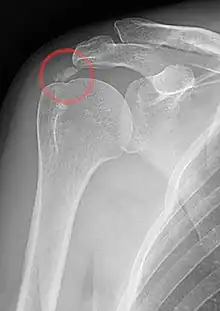

A plain X ray of the shoulder showing calcific tendinitis

Calcific tendinitis is a common condition where deposits of calcium phosphate form in a tendon, sometimes causing pain at the affected site. Deposits can occur in several places in the body, but are by far most common in the rotator cuff of the shoulder. Around 80% of those with deposits experience symptoms, typically chronic pain during certain shoulder movements, or sharp acute pain that worsens at night. Calcific tendinitis is typically diagnosed by physical exam and X-ray imaging. The disease often resolves completely on its own, but is typically treated with non-steroidal anti-inflammatory drugs to relieve pain, rest and physical therapy to promote healing, and in some cases various procedures to breakdown and/or remove the calcium deposits.